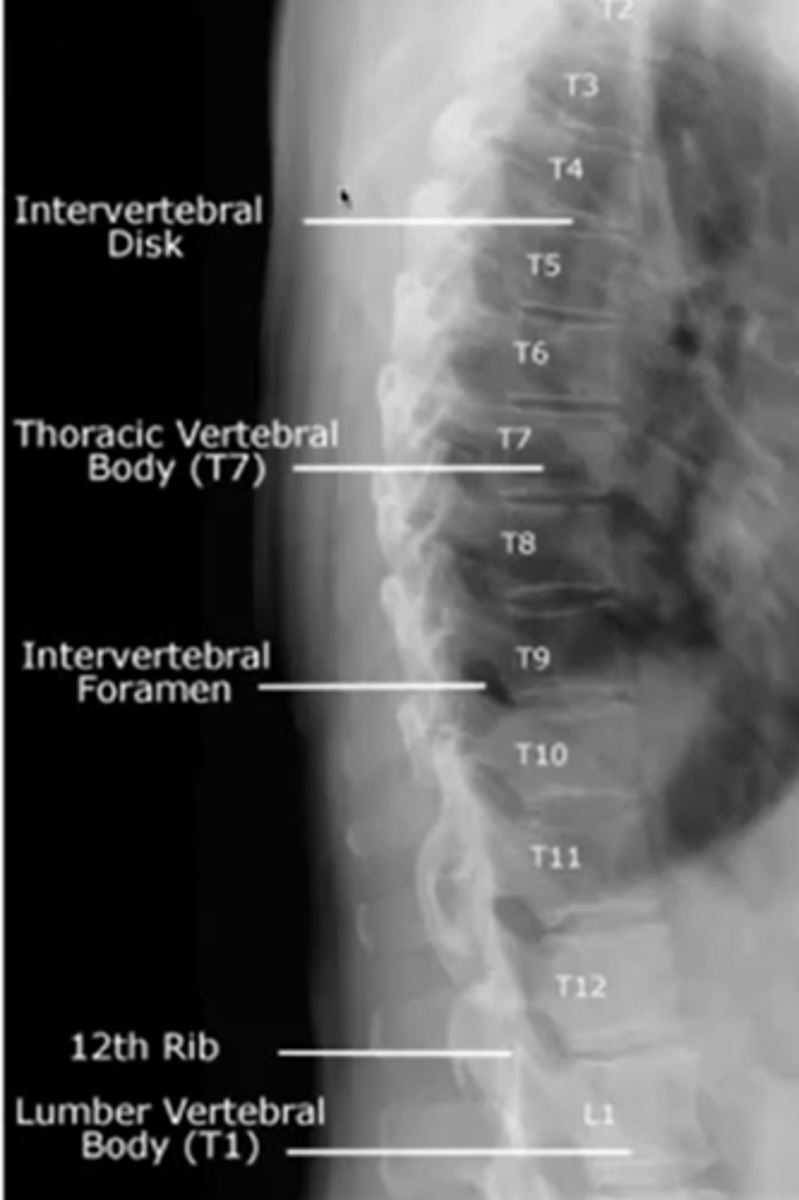

when looking at the thoracic spine

what view should you choose to see

vertebral bodies

AP

transverse process

spinous process

pedicles

lateral

intervertebral disc height

intervertebral foramina

what are the three lines for the thoracic spine